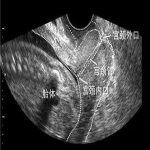

宫颈松弛检查-扩宫试验

扩宫试验,是诊断宫颈内口松弛的最可靠诊断技术。在非经非孕期,用8号扩宫棒,依次递减,试扩宫口。

扩宫试验

正常标准:5号扩宫棒不能自由通过宫颈内口。北京安太医院当天可以确诊!明确诊断可以签约治疗。